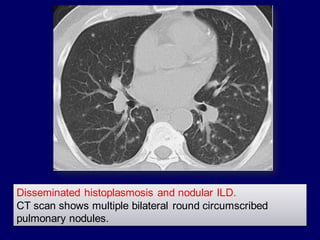

Disseminated histoplasmosis and nodular ILD.

CT scan shows multiple bilateral round circumscribed

pulmonary nodules.

Notice the nodules along the fissures indicating a

perilymphatic distribution (red arrows).

The majority of nodules located along the bronchovascular

bundle (yellow arrow).

Sarcoidosis

The majority of nodules located

along the bronchovascular bundle

(yellow arrow).